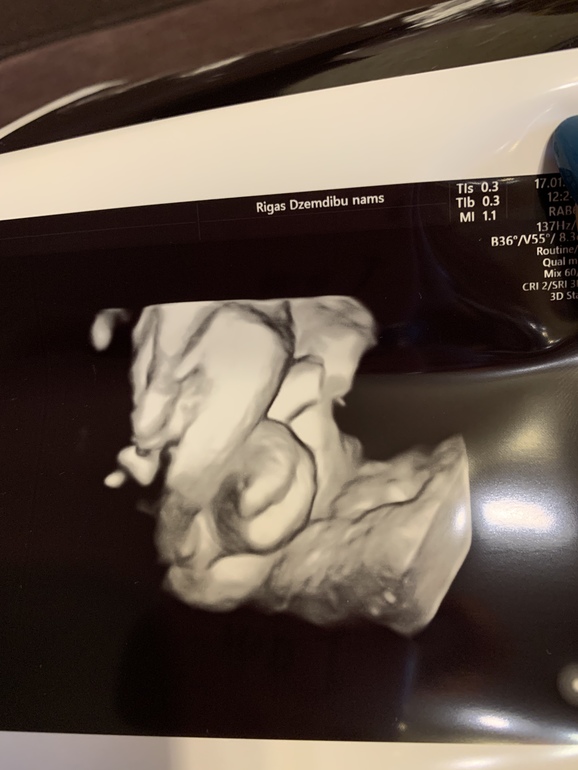

А тем временем идёт 31-я неделя. По плоду 32-я... Я больше не работаю. И понимаю, что лень напала))) Валяюсь дома, гуляю редко. Постоянно за рулем. А надо бы чаще бывать на свежем воздухе. Сегодня была на УЗИ. Плод, по всем параметрам соответствует 33 полным неделям! Опять ждать мне слонёнка))) Ну и фото нас на память. И просто и с узи.

У него все классно)))

Пускаем пузыри)))